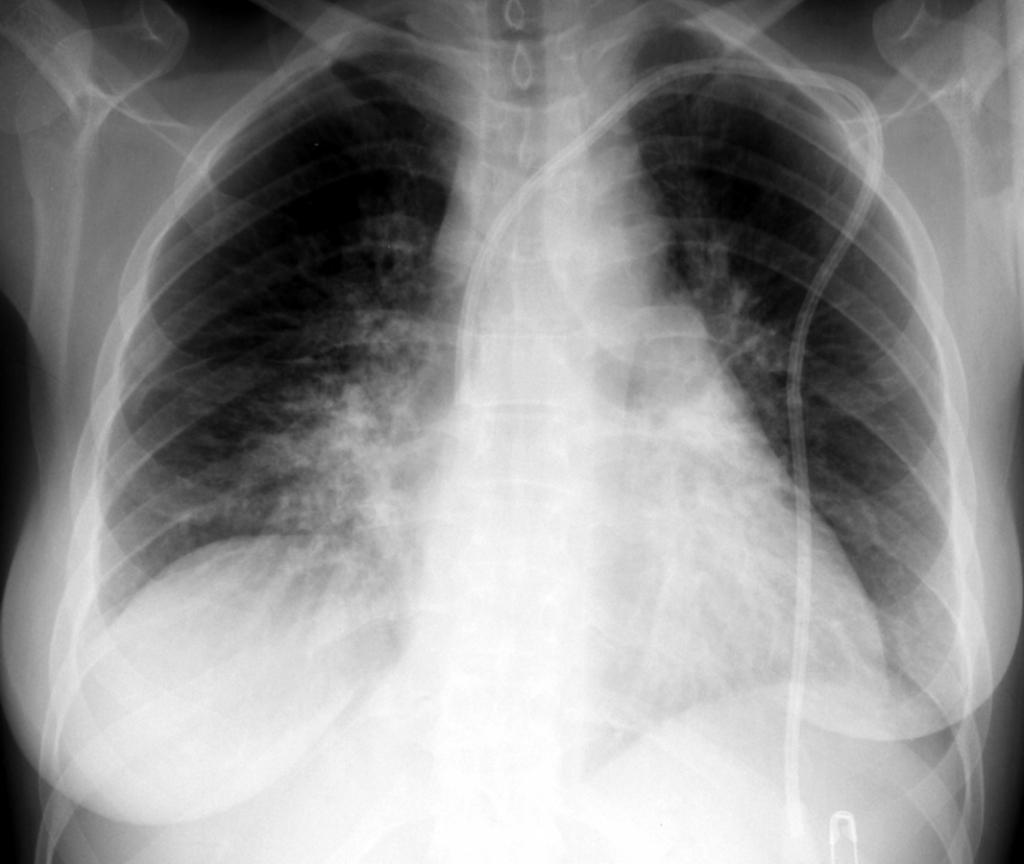

Первичная диагностика предполагает прежде всего сбор анамнеза наряду с физикальным осмотром, оценкой состояния кожных покровов, измерением пульса и давления у пациента. Основной методикой, позволяющей диагностировать синдром ателектаза, служит рентген. На рентгеновских снимках обнаруживаются признаки спадания легочных тканей, к которым относится:

- Присутствие затемнения однородного характера в пораженном районе. Его размеры с формой могут различаться и зависят от типа патологии. Наличие обширного затмения, обнаруженное при рентгене, свидетельствует о долевом ателектазе легкого.

- Присутствие смещения органов. За счет давления, которое оказывается пораженной стороной, расположенные между легкими органы смещаются в сторону здорового участка.

Диагностика ателектаза легкого довольно проста. Рентген дает возможность обнаружить, куда именно смещаются органы при дыхании, а также во время кашля. Этот фактор тоже определяет тип заболевания. Иногда рентген дополняют проведением компьютерной томографии или бронхоскопии. Уровень поражения легких наряду со степенью деформации бронхов и состоянием сосудов определяют бронхографией, а кроме того, ангиопульмонографией.

Тогда как замедленное развитие ателектаза сопровождается малозаметными клиническими проявлениями и для выявления необходима рентгенография. Оно может привести к склеротическим изменениям легочной ткани – так называемому фиброателектазу.